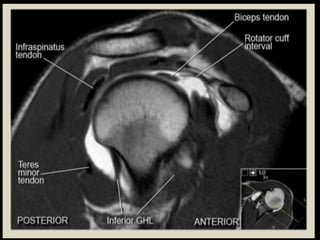

Shoulder

Joint.